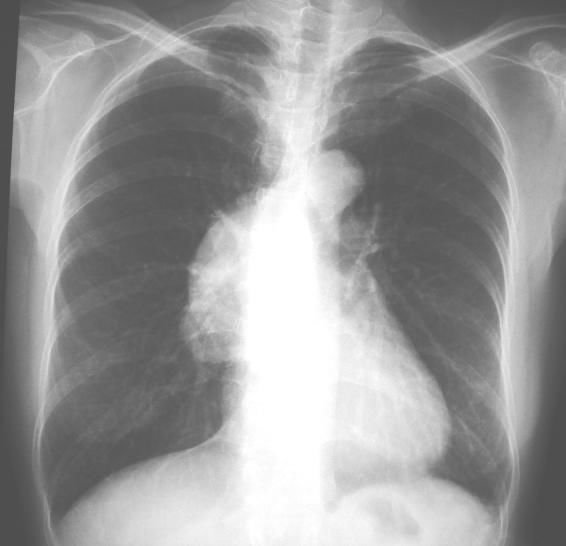

3. 一位60歲男性,長期咳嗽有痰,走路時會喘,聽診顯示左肺呼吸音較小,胸部X光如圖所示。請問他罹患何種疾病?

(A) 氣管狹窄 (B) 心臟衰竭 (C) 左肺氣腫 (D) 左肺下葉扁塌 (E) 氣喘病